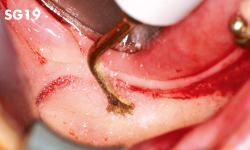

Nivelación de la cresta alveolar o escisión ósea.

Eliminación de tejido de granulación de la zona de extracción.

• POTENCIA [SURG] 80%

• Revestimiento de TiN

• Punta con borde de espátula redondeada

• Instrumento de un solo filo